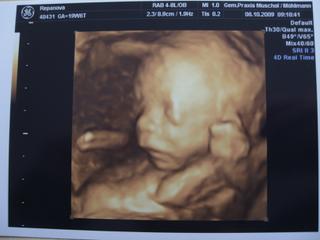

Inak vam poviem, ze to tehotenstvo mi hrozne chyba. MM uz hovori ze je nacase zamiesit na druhe 😵